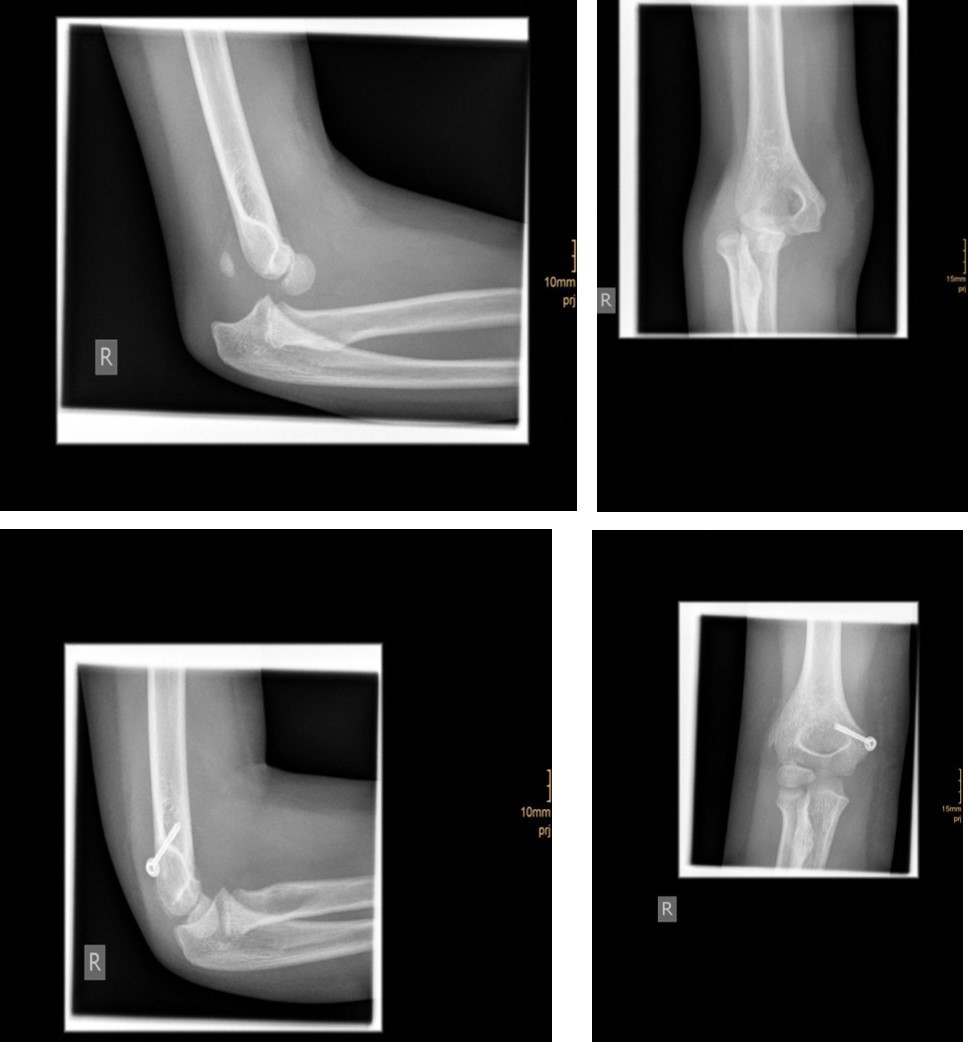

The degree of displacement may be seen on the true lateral view. In determining whether the articular hinge is intact (i.e., stage I vs. stage II), the relationship of the proximal ulna to the distal humerus is evaluated for the presence of lateral translocation. Oblique views are especially helpful in patients in whom a stage I displacement is suspected but not evident on AP and lateral views. Figure 1 and Figure 2.

Figure 1.6 year old male patient with a undislocated left lateral condyle fracture which was succesfully treated with a cast (personal collection)

Figure 2.6 year old male patient with a dislocated right lateral condyle fracture which was treated by open reduction and osteosynthesis with a screw and a Kirschner wire (personal collection)

Non-displaced and stable fractures may be treated by cast immobilization with close follow-up, but fractures displaced >2 to 3 mm may indicate surgical fixation 7, 8. Surgical treatment can be done either by closed reduction and percutaneous osteosynthesis or open reduction and osteosynthesis. Figure 3.

Figure 3.9 year old male patient with a elbow dislocation and a dislocated left lateral condyle fracture which was treated by open reduction and osteosynthesis with a screw (personal collection)